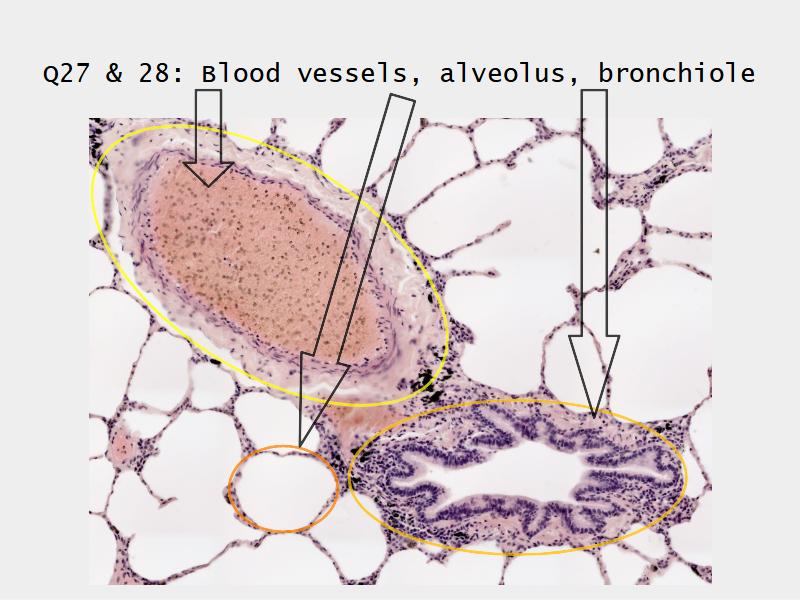

Slides: Respiratory System

- Slide 72 & 74: Lung

Bronchi - Transitions

- Intrapulmonary bronchi

- Irregular cartilage

- Respiratory epithelium

- Glands

- Bronchioles

- Smooth muscle REPLACE cartilage

- Ciliated columnar > Ciliated cuboidal

- NO glands - goblet cells -> secretory cells

- Alveoli

Lungs